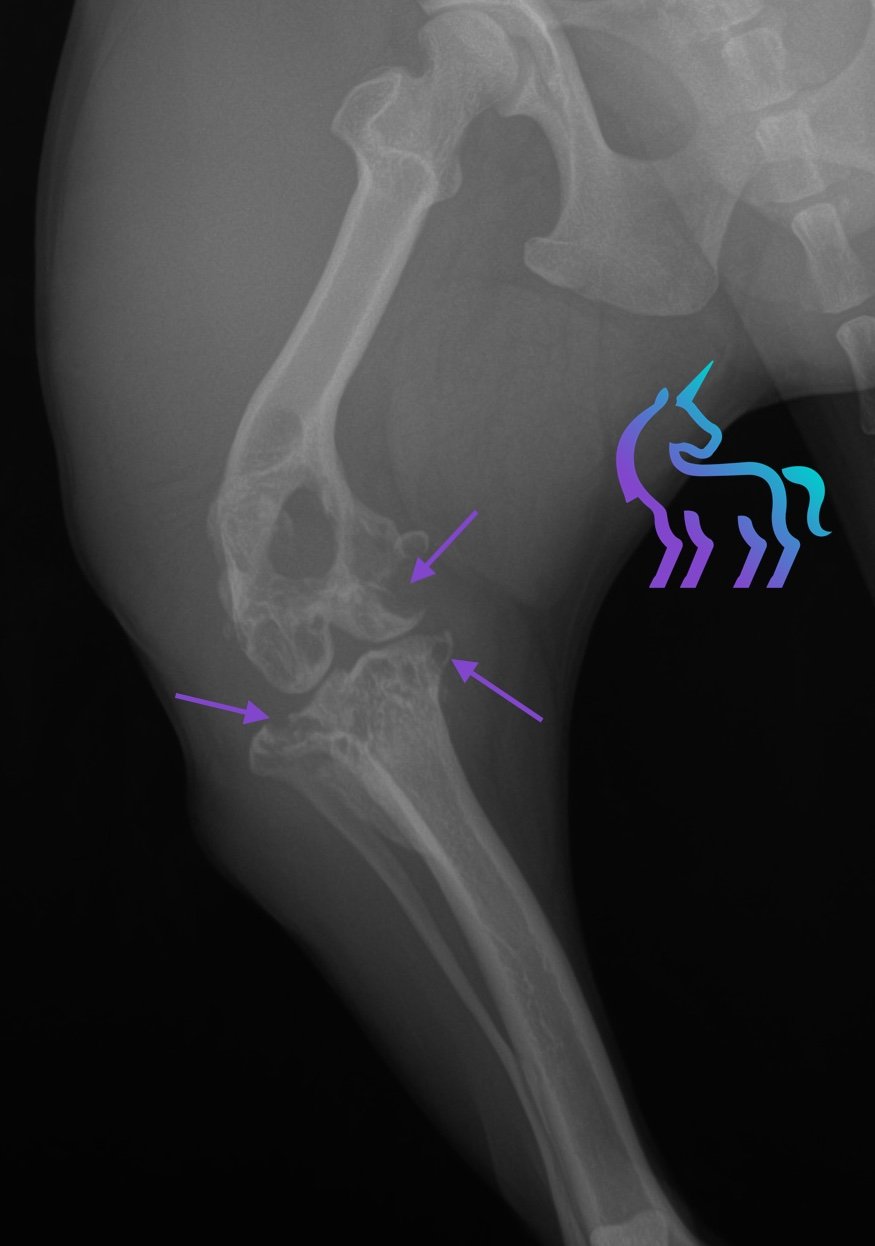

Processus tumoral ostéo-articulaire du grasset droit

Espèce : ChienRadiographies du grasset droit montrant une masse ostéolytique articulaire associée à une tuméfaction des tissus mous, sans métastase pulmonaire visible au bilan thoracique.

L’aspect est compatible en priorité avec un sarcome articulaire (notamment sarcome histiocytaire).

Diagnostic retenu : La radiographie permet ici de poser un diagnostic de tumeur osseuse agressive du grasset et d’orienter la prise en charge thérapeutique.